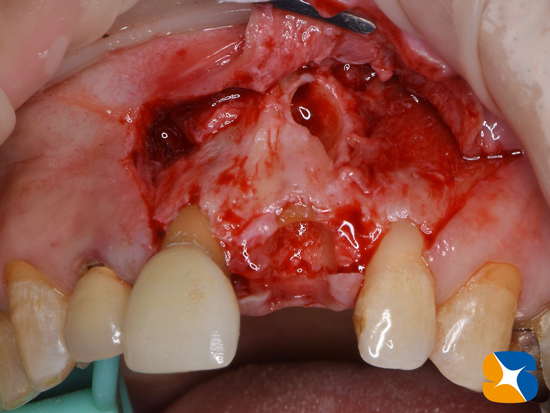

抜いた歯の根の周りは、かなり大きく骨が欠落していました。

CTを用いて入念にチェックしていましたが、これは想定外でした。

再度6ヶ月待って骨だけを作るべきか、インプラント移植と同時に骨の再建に取り組むか悩みました。

前者を選ぶと、おそらく患者様は半年間も奥歯の無い生活に不満が出ることでしょう。

それを考えると、後者のインプラント移植と骨の再建とを同時に取り組むことにしました。

水色の2箇所の予定場所(=写真=)の中間位置に太めにインプラントを移植することにしました。

インプラント移植と骨の増殖を同時に行いました。

骨の増殖には、人工骨β-TCPとCGF(フィブリノーゲン)を混ぜた物を使用しています。

人工骨の変形や流出を避けるために、CGFメンブレンを利用しました。